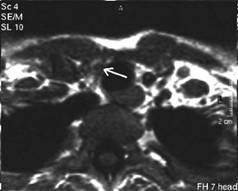

Mica formatiune nodulara medial de carotida dreapta (0,2 cc), marcat

hipoecogena.

Tireoglobulina: < 2 ng.

Examen citologic: carcinom papilar.

Aceeasi pacienta - hipervascularizatie interna la doppler color si powerdoppler

Aceeasi pacienta cu mica formatiune

nodulara medial de carotida dreapta - IRM